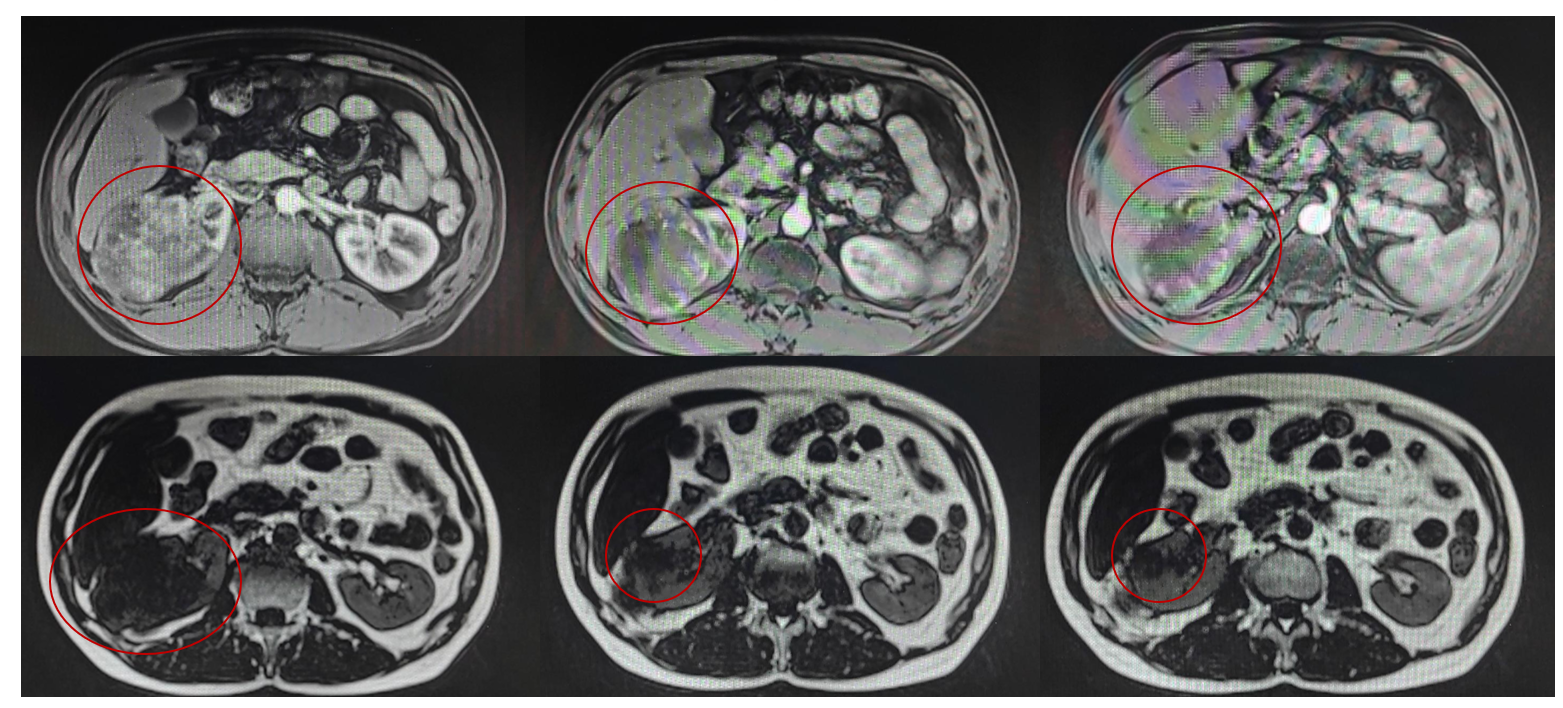

2023-09-01全腹增强MRI: 右肾见一类椭圆形肿块,大小约80mm×65mm×74mm,呈等稍长T1、等长T2信号、弥散受限,增强扫描明显强化、强化不均匀,右肾盂受压变形,病灶累及肾周间隙及肾后筋膜,肾后筋膜增厚毛糙呈结节样,部分肾静脉稍显不清,肾血管旁见数个小淋巴结显示,大者短径约4mm;以上考虑右肾肿瘤占位,透明细胞癌?预计分期T3aNOMx。

免疫组化: PAX8(+), CAIX (+),CD10(+), CK (+),CD117(少许+),CK20(-),CK7(-), CgA (-),HMB45(-),S100(-),TFE3(-), syn (-/+),Ki67(约30%)。结合组织形态及免疫组化结果,符合肾细胞癌。

透明细胞肾细胞癌( WHO :3-4级)。

治疗经过

手术治疗:

2023-09全麻全麻下行腹腔镜下右肾根治性切除术、肾周粘连松解术。

术后病理:透明细胞肾细胞癌( WHO / ISUP :3级)。

药物治疗:

2023-09培唑帕尼治疗至今;

2024-04腹部增强CT;

疗效评估:SD。